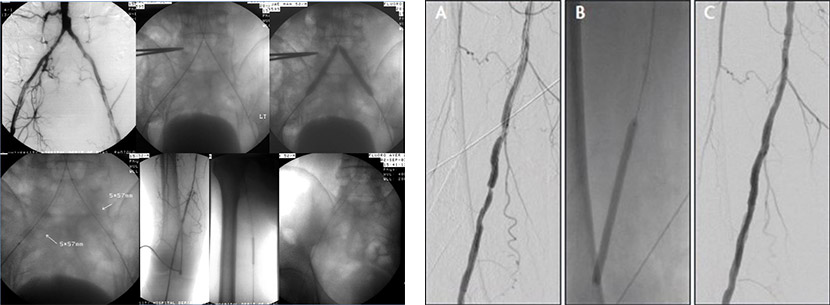

1.혈관성형술

당뇨, 동맥경화, 혈관염 등의 혈관 질환으로 인하여 혈관이 좁아지거나, 막히거나, 풍선처럼 늘어나거나, 찢어지는 등의 현상이

생길 수 있습니다. 이 경우 수술이 없이도, 서로 연결되는 혈관 속을 타고 들어가 해당 부위로 카테터를 접근시킨 후

풍선이 내장된 관이나 스텐트라는 팽창형 그물망으로 좁은 부위를 넗히거나, 막힌 부위를 뚫거나, 풍선처럼 늘어난 부위를 성형하거나,

찢어진 부위를 막는 치료를 할 수 있습니다. 이러한 치료를 내혈관적 혈관성형이라고 합니다.

당뇨, 동맥경화 등으로 하지동맥이 막혀 다리가 썩거나 쉽게 저리는 경우가 생길 수 있습니다.

이런 경우(부위에 따라서 치료 방침이 조금씩 다르지만) 혈관 성형술 단독으로 또는 수술과 같이 병행하여 좋은 효과를 볼 수 있습니다.

정맥의 경우에는 다리의 정맥이 혈전으로 막히거나, 동맥에 의하여 눌려 좁아져서 혈류가 원활하지 않아 다리가 붓는 경우가 있습니다.

이 경우 막힌 혈전을 녹이고, 좁아진 부의를 넓히는 치료를 할 수 있습니다.

신동맥(콩팥으로 가는 동맥)이 좁아지는 경우 신기능이 저하되고 심한 고혈압이 옵니다. 이런 경우에도 수술 없이 치료가 가능합니다.

2. 혈액투석 동정맥루의 혈관 성형 치료

혈액투석 환자에게는 팔의 동정맥루가 생명선과도 같습니다. 그러나 오랜 기간 동안 이를 이용하여 투석 치료를 하면

어쩔 수 없이 동정맥루의 길이 좁아지거나 막혀서 사용하기가 힘들게 됩니다. 심한 경우에는 팔 정맥 자체가 막혀서 팔 전체가

심하게 붓게 되는 일이 생길 수 있습니다. 이런 경우 재수술을 하게 되면 사용 가능한 팔의 혈관이 자꾸 없어지게 되므로,

가능한 한 고쳐서 사용하는 것이 좋습니다.

혈관성형술은 간단하게 혈관 내로 가느다란 관을 삽입하여 혈전을 녹여 막힌 부분을 뚫고 좁아진 부위를 넓혀서 혈류를 회복시켜주는

시술입니다.